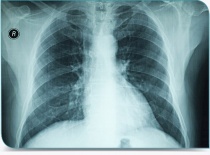

• radio du thorax (évaluer le volume et la position du cœur),